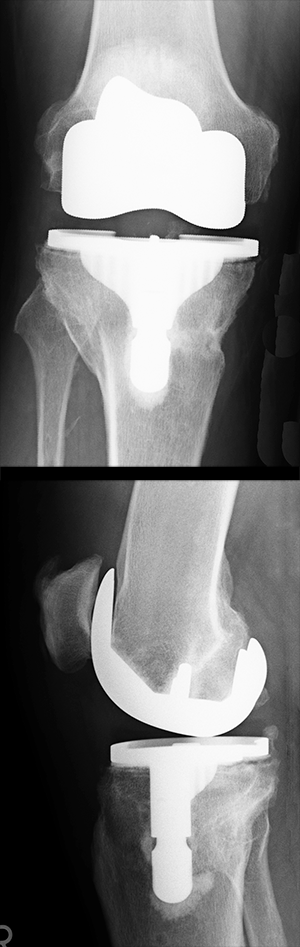

Da die künstlichen Gelenkoberflächen zum Teil aus Metall bestehen, kann man sie sehr gut im Röntgenbild darstellen.

Hier ist eine Totalendoprothese, also ein kompletter Oberflächen-Ersatz des Kniegelenkes zu sehen. Oben Ansicht von vorne, unten von der Seite. Das Bild hier ist in Ordnung. Bei Lockerung der Prothese (sehr ärgerlich!) wäre ein dunkler Saum zwischen Metall und Knochen zu sehen.